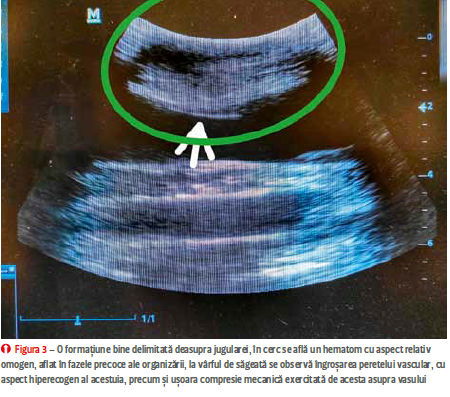

cu perete ceva mai hiperecogen în cea longitudinală. În caz de inflamație, se poate observa îngroșarea peretelui vascular, cu acumulare de lichid și / sau gaz în țesutul subiacent fie sub formă de edem sau de hematom (figura 3) și eventual prezența unui trombus, reprezentat

de către o structură hiperecogenă, relativ omogenă, atașată de cel puțin unul din pereții vasului. Capătul trombusului poate fi neted, bine demarcat (în cazurile cronice) sau cu un aspect șters, indistinct (cazurile acute). Un trombus septic este caracterizat de un aspect heterogen,

iar dimensiunea si extensia sa la nivelul structurilor anatomice adiacente pot fi urmărite cel mai bine cu ajutorul secțiunii longitudinale. Se poate utiliza ecografia Doppler (pulsed wave sau color flow) pentru a pune în evidență fluxul sanguin

(figura 2);

.png)

în lipsa lui, unele sonde cu frecvență înaltă pot pune în evidență fluxul laminar. Cazurile unde suspiciunea obliterării totale nu este confirmată ultrasonografic (fibrozări extensive, leziuni locale greu de pus în evidență) pot fi evaluate cu ajutorul ultrasonografiei cu substanță de contrast. Trombozele acute se rezolvă fie prin intermediul proceselor de fibrinoliză cu dizolvarea parțială sau totală a trombusului și recanalizare, sau prin fibrozarea acestuia și cu obstrucția vasului afectat (figura 4).